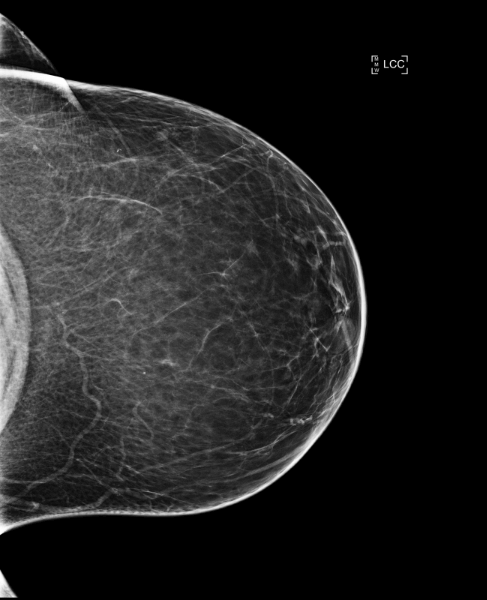

Cas de la semaine (semaine 45, 2023)

Dépistage en 2020 d’une patiente de 65 ans

Le radiologue a eu accès à un large historique d’examens antérieurs, le plus récent étant réalisé un an plus tôt. Les seins sont peu denses (densité A).

Au cours de la lecture de la mammographie, le radiologue trouve une asymétrie et une possible distorsion suspecte sur le sein droit en CC, à la fois sur la 2D et sur la tomosynthèse, sans trouver de correspondance en MLO.